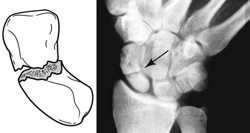

Illustration and x-ray showing a break in the mid-portion, or "waist," of the scaphoid. This is the most common location for a fracture.

Reproduced with permission from JF Sarwark, ed: Essentials of Musculoskeletal Care, ed 5. Rosemont, IL, American Academy of Orthopaedic Surgeons, 2016.